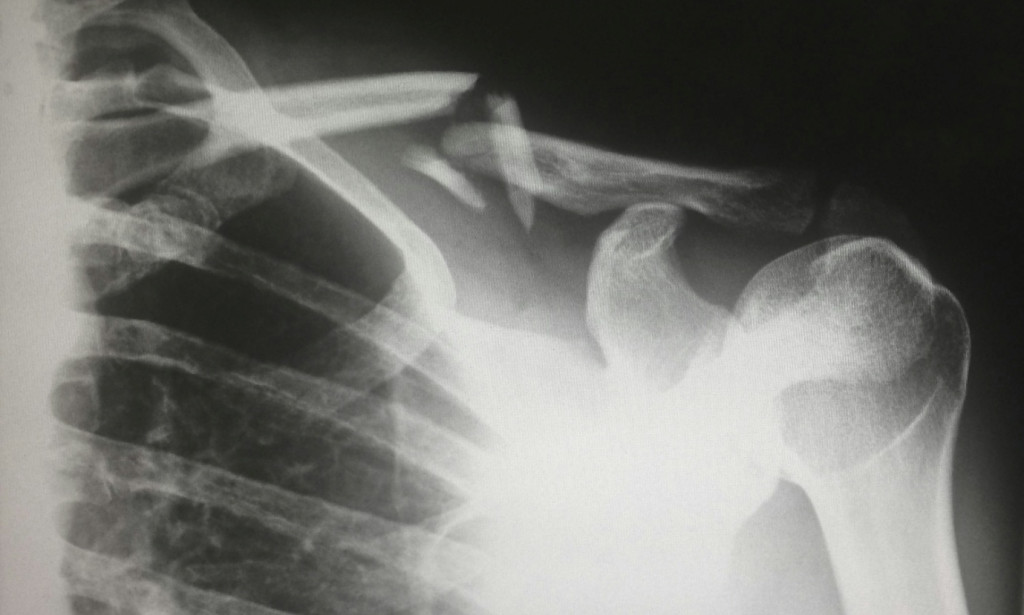

Image Caption: Bone scans and X-rays can lead to soreness and fatigue.